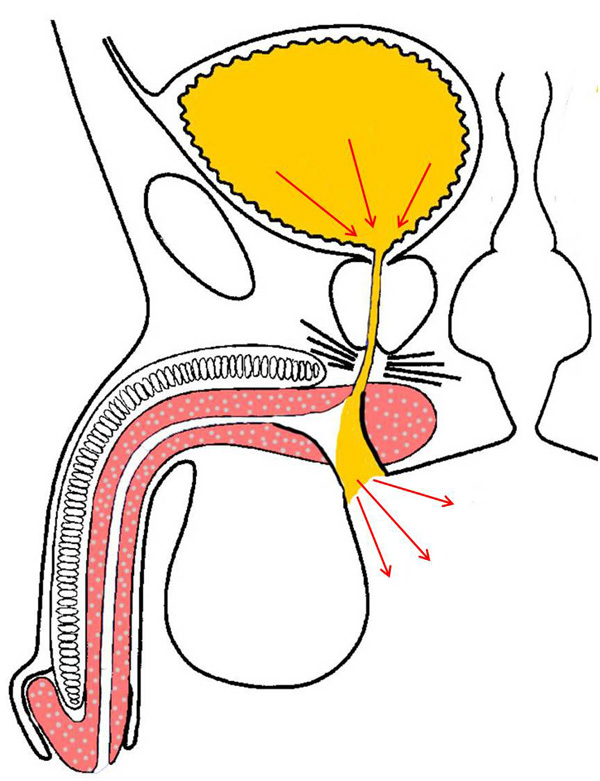

Учащённое мочеиспускание с сильным позывом Аноним 02/01/26 Птн 22:46:30 1653827 Ответ

image.png 368Кб, 600x781

600x781

После промежностной уретропластики я стал ощущать очень сильные позывы к мочеиспусканию в уретре, когда объём мочевого пузыря заполняется на 200-250 мл. Эти позывы стихают, но затем опять повторяются. Доходит до того, что позыв невозможно сдержать. Уролог нихуя не говорит, только говорит делать упражнения Кегеля, они не убирают ощущение "хочу поссать щас обоссусь". Что можно сделать?